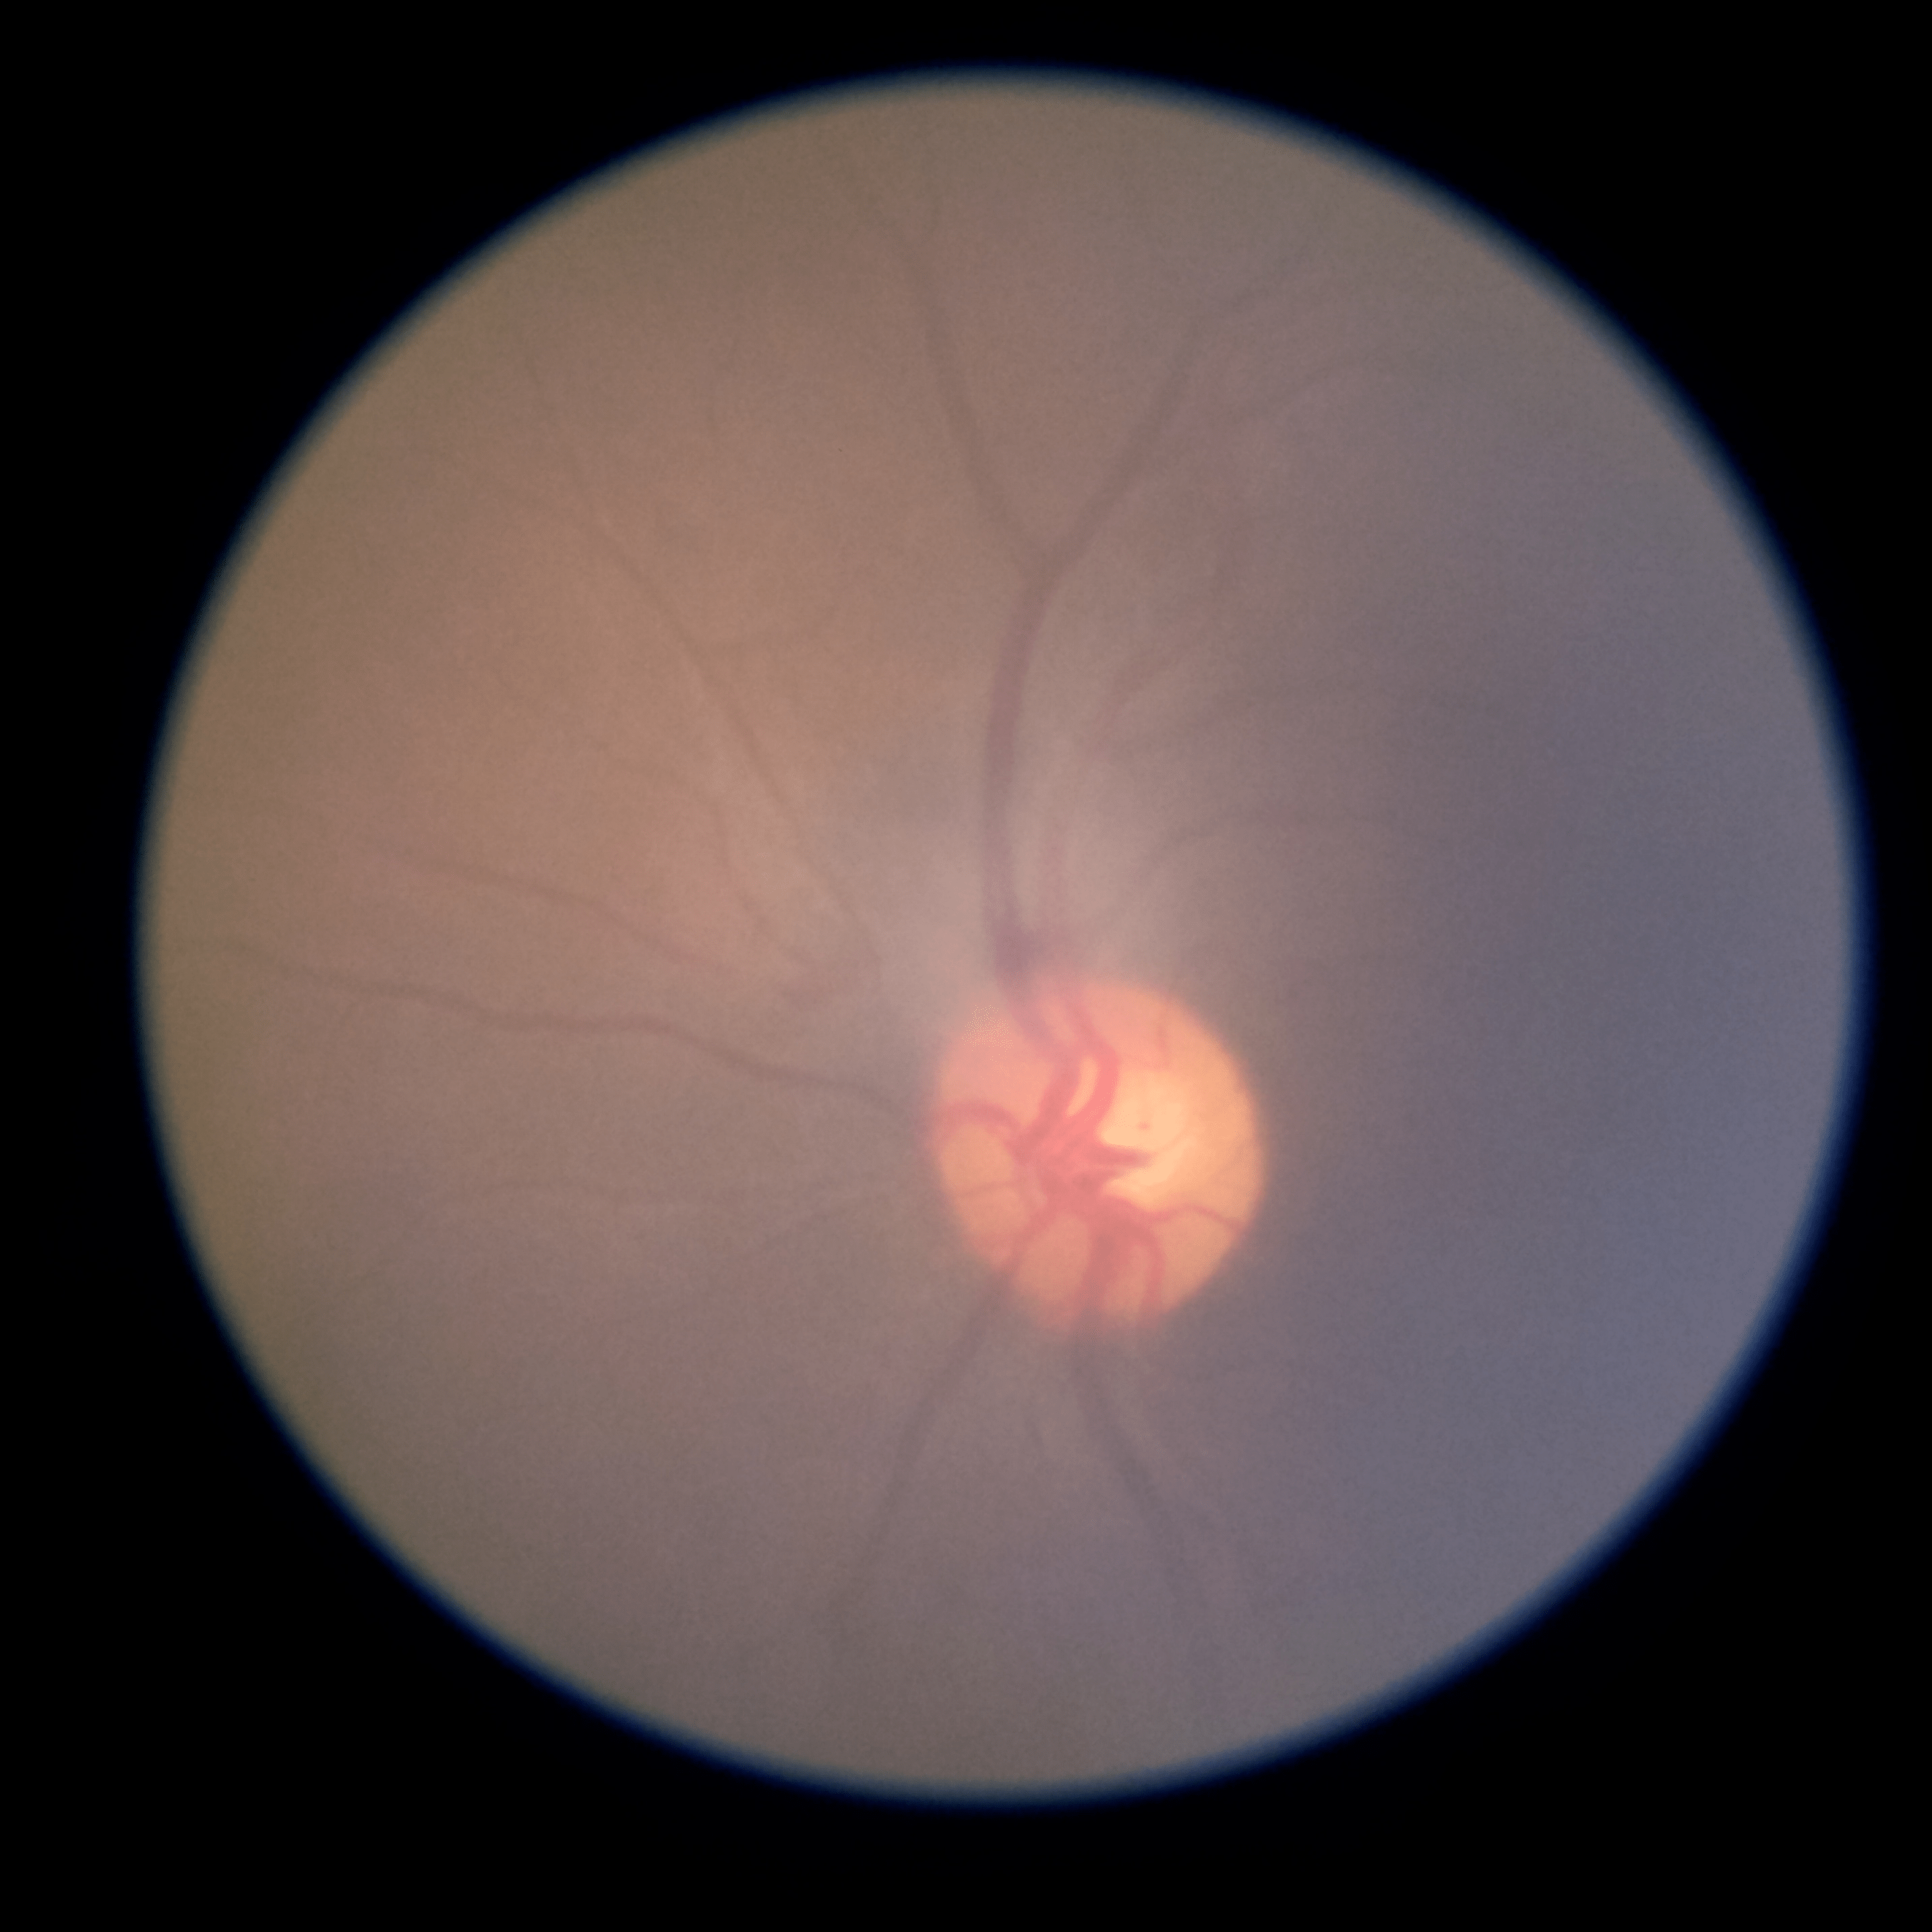

1. The core of each dataset is a large collection of medical images: x-rays, ECG waveforms, digital pathology (and more to come). These rich, high-dimensional signals are too complex for humans to fully see or process—so machine vision can add huge value.